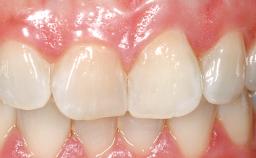

Late Flapless Placement of an Implant in a Maxillary Left Central Incisor Site

A 39-year-old male patient presented with a chief complaint of discomfort and gingival discoloration around his maxillary left central incisor. He was in good general health and was a non-smoker. His past dental history was significant because of the traumatic fracture of tooth 21 in a sporting accident at age 13. Initial dental treatment included endodontic therapy and a full-coverage restoration. The patient became symptomatic 5 years later, when structural failure of the tooth resulted in the dislodgment of the crown. Endodontic retreatment, apical surgery, and post-and-core restoration were performed.

Prosthesis Type FDP

SAC Level Advanced

Defining Characteristics One missing tooth to be replaced by an implant-borne crown

Esthetic Risk High